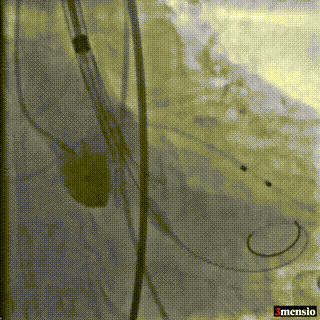

释放初始位提高2mm左右释放,造影观察位置

释放到2/3工作位,观察是否会位移

瓣膜锚定稳固,在起搏状态下缓慢脱钩,同时轻顶输送器卸张力